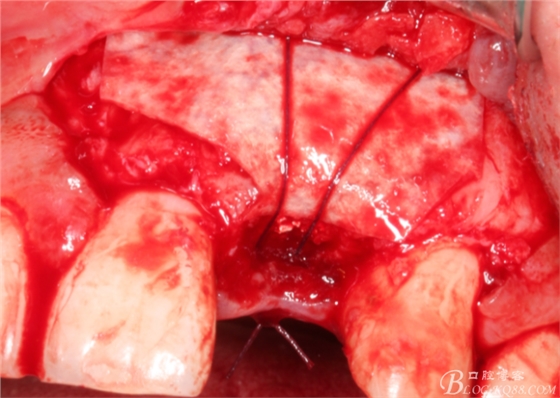

先行粘骨膜減張,取自體血液。

根方用取骨鉆取自體骨。

旋入一長兩短3顆鈦釘。

將自體骨與BIO-OOS骨粉混合植到術(shù)區(qū),蓋生物膜。

縫合。